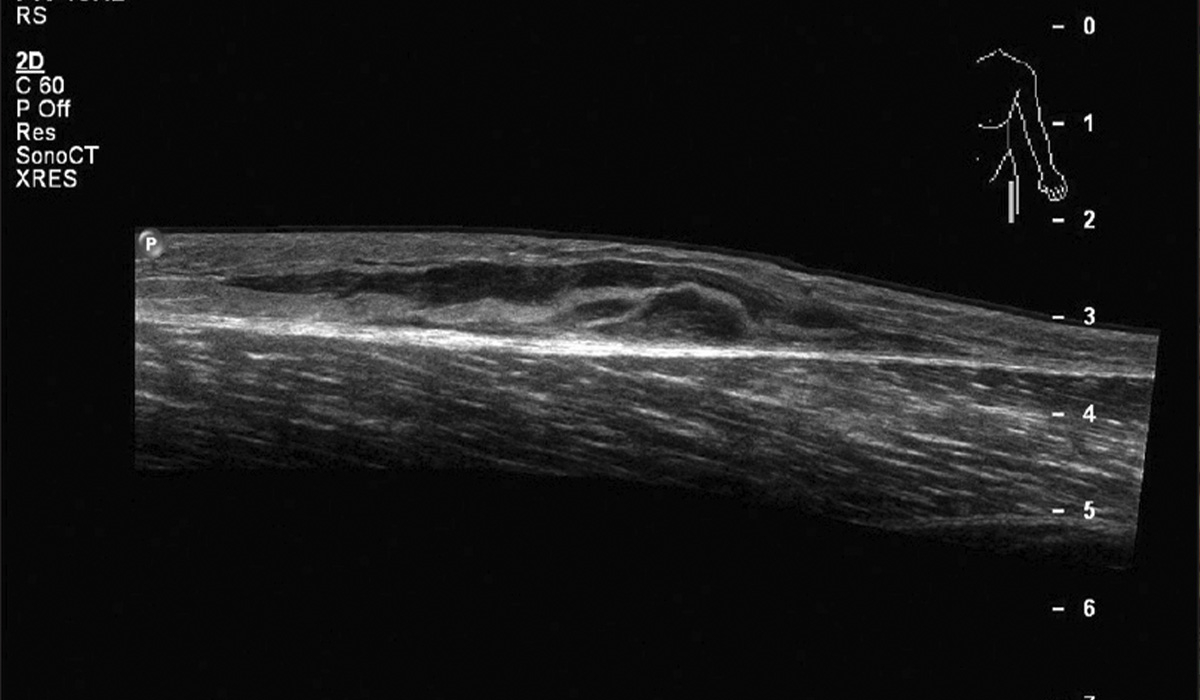

УЗД дає чітке зображення найдрібніших структурних елементів, дозволяє побачити сухожилля на всіх рівнях кінцівки, периферичні нервові стовбури до рівня основних фаланг пальців.

- розрив сухожиль;